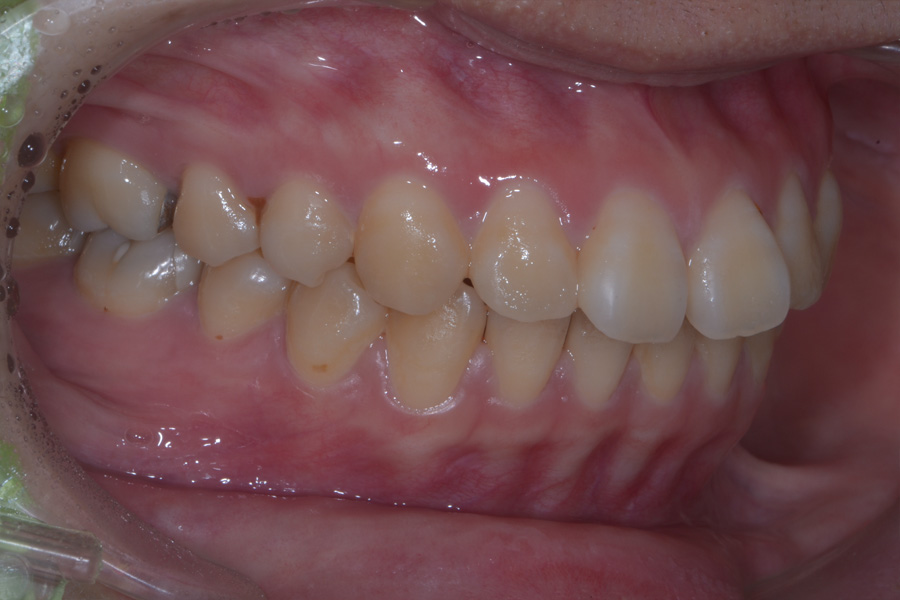

治療前

主訴 出っ歯とすきっ歯を治したい

治療内容 上顎ラビアル矯正(表側矯正)